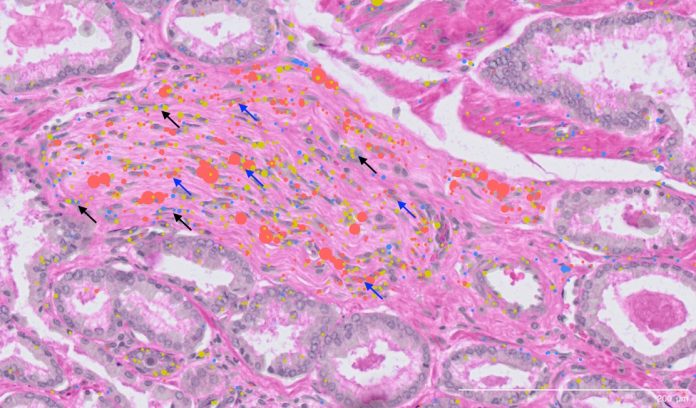

Cercetătorii au analizat probe de biopsie de la 24 de pacienți diagnosticați recent cu cancer de prostată în stadiu incipient. Toate probele au fost obținute de la Biobanca de Cancer de Prostată Garvan St Vincent, care păstrează material de la peste 16.000 de pacienți. Secvențierea ARN-ului la nivelul unei singure celule și transcriptomica spațială au fost utilizate pentru a examina atât celulele canceroase de prostată, cât și mediul înconjurător, creând o imagine completă a compoziției lor moleculare și distribuției spațiale.

Au fost identificate un total de 11 tipuri majore de celule, 50 de subtipuri minore și numeroase stări celulare, unele dintre ele unice pentru fiecare individ și altele comune între pacienți. Aceasta a dus la identificarea unei noi populații de celule pe care cercetătorii le-au numit fibroblați asociati cancerului perineural, localizați în apropierea nervilor. Deoarece tumorile de prostată care cresc în și în jurul nervilor sunt asociate cu rezultate mai slabe, această descoperire ar putea oferi un punct de plecare pentru a înțelege mai bine rolul lor în metastaza cancerului de prostată.

„Am reușit să clasificăm aceste celule la nivel molecular pentru prima dată, oferindu-le o identitate distinctă”, a spus Swarbrick. „Acești fibroblaști perineurali în tumori par să aibă un mecanism specializat pentru a comunica cu nervii. Încă nu știm cum acest lucru influențează progresia bolii, dar este un domeniu promițător de cercetare.”